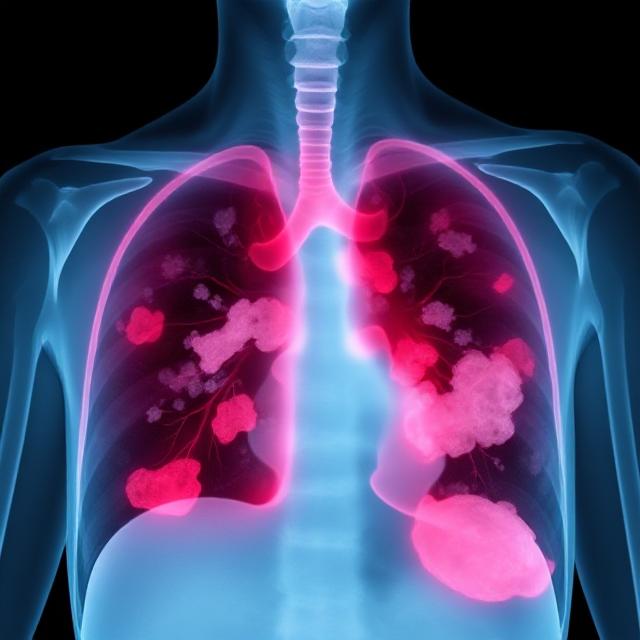

آب آوردن ریه که در اصطلاح پزشکی به آن پلورال افیوژن گفته می‌شود، یک وضعیت جدی است که در آن مایع در فضای بین ریه و دیواره قفسه سینه جمع می‌شود. این مشکل می‌تواند تنفس را دشوار کند و در صورت عدم درمان به مشکلات جدی‌تری منجر شود. در ادامه، به بررسی علت‌ها، علائم، روش‌های درمان و نکات مراقبتی خواهیم پرداخت.

آب آوردن ریه می‌تواند ناشی از شرایط مختلف باشد، از جمله بیماری‌های قلبی، عفونی و سرطانی. رایج‌ترین علل عبارت‌اند از:

علائم آب آوردن ریه ممکن است به تدریج ظاهر شوند یا ناگهانی باشند. شایع‌ترین علائم عبارت‌اند از: